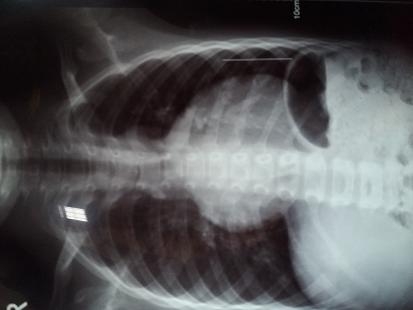

小孩术后5年,最近久咳不止。胸片显示心影增大成球形,心胸比约0.61。

彩超报告: 2016年心脏彩超结果为:1、右心增大;2、三尖瓣返流轻度;3、肺动脉版返流轻中度。

从胸片上看,心脏还是偏大了一些,建议还是继续随访复查吧。